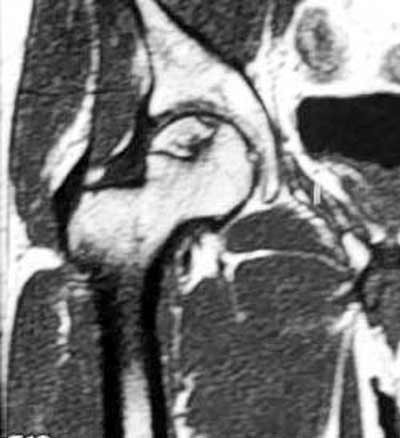

Tout oriente vers une épiphysiololyse de la hanche :

– la douleur chronique, localisée au genou avec toutefois un examen clinique du genou normal

– la position vicieuse du membre inférieur en rotation externe

– la limitation de la mobilité de la hanche, principalement en abduction et rotation interne

– le patient est un jeune homme en période pubertaire, avec un surpoids